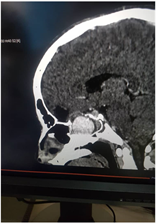

A cranio-cerebral CT scan with injection of contrast product found a rounded mass at the level of the sphenoid sinus, measuring 30 × 27 × 22 mm (9.26 cc) This mass was strongly enhanced after injection of contrast product, communicating with the left ICA at level of its cavernous part. There was a mass effect on the left superior orbital fissure with an increase in the size of the left ophthalmic artery. Furthermore, we noted grade II exophthalmos and left frontal cortico-subcortical hypodensity and discontinuity of the ethmoid cells and the lateral wall of the sphenoid sinus, probably residual. At finally, we have concluded to a left carotid-cavernous fistula on aneurysm, type A according to the angiographic classification of Barrow et al. (Figure 1).

(a) (b) (c)

Figure 1. Craniocerebral CT scan of the patient (a): Axial section through the orbital apexes. Grade II exophthalmos (b) and (c): Sagittal sections. Contrast, bone lysis.